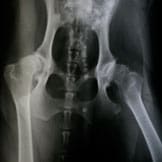

Hip Dysplasia

This deteriorating bone ailment mainly affects larger canine breeds. Learn what symptoms to watch for and what treatment options are available.